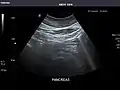

Ultrasound can be used for additional anatomical information for patients with an abnormal kidney function or pancreatic enzymes (pancreatic amylase and pancreatic lipase).

Pancreas: Visualized portions unremarkable.